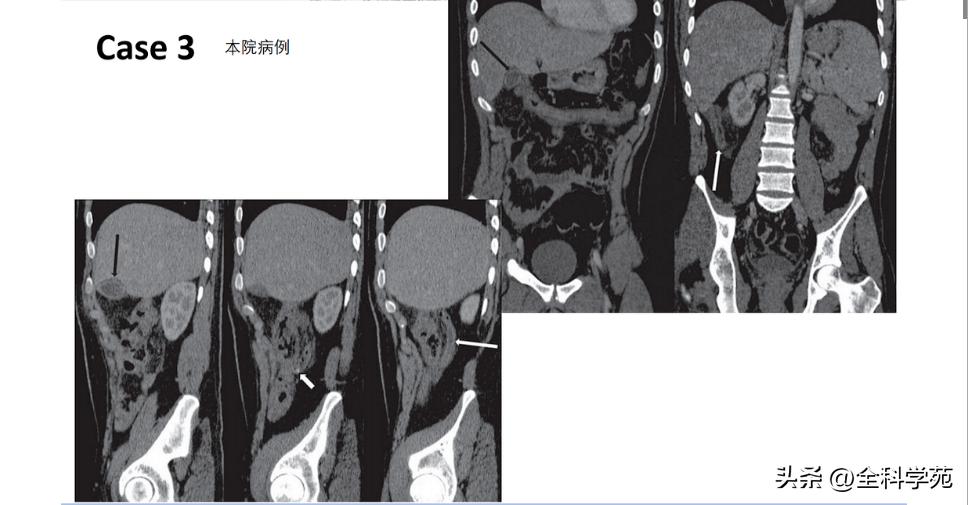

◆ 阑尾壁增厚

>3mm

CT: 阑尾壁明显增强

◆ 阑尾的内径增宽

> 10 mm

6-10 mm 伴阑尾壁增厚、壁明显强化,周围脂肪间隙模糊或分层(靶征或牛眼征,表明粘膜下水肿的液体含量vs 气体含量

◆ 阑尾周围脂肪密度增高/模糊与腹腔其他部位的脂肪比较,CT表现为脂肪密度增高,T2压脂为高信号